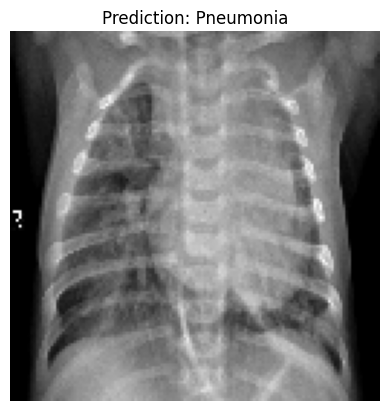

import numpy as np

from tensorflow.keras.preprocessing.image import load_img, img_to_array

import matplotlib.pyplot as plt

# Load a sample image from the test dataset

sample_image_path = 'chest_xray/chest_xray/test/PNEUMONIA/person100_bacteria_475.jpeg'

sample_image = load_img(sample_image_path, target_size=(128, 128))

sample_image_array = img_to_array(sample_image) / 255.0

sample_image_array = np.expand_dims(sample_image_array, axis=0)

# Make a prediction

prediction = model.predict(sample_image_array)

# Display the image with the prediction

plt.imshow(sample_image)

plt.title(f"Prediction: {'Pneumonia' if prediction[0][0] > 0.5 else 'Normal'}")

plt.axis('off')

plt.show()1/1 ━━━━━━━━━━━━━━━━━━━━ 0s 95ms/step

we have successfully trained and tested our CNN model for pneumonia detection.